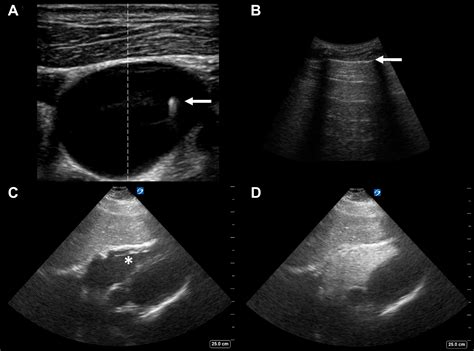

Pectoral Muscle Torn: Causes, Symptoms, and Treatment - Alinea

Pectoral Muscle Torn: Causes, Symptoms, and Treatment - Alinea ...